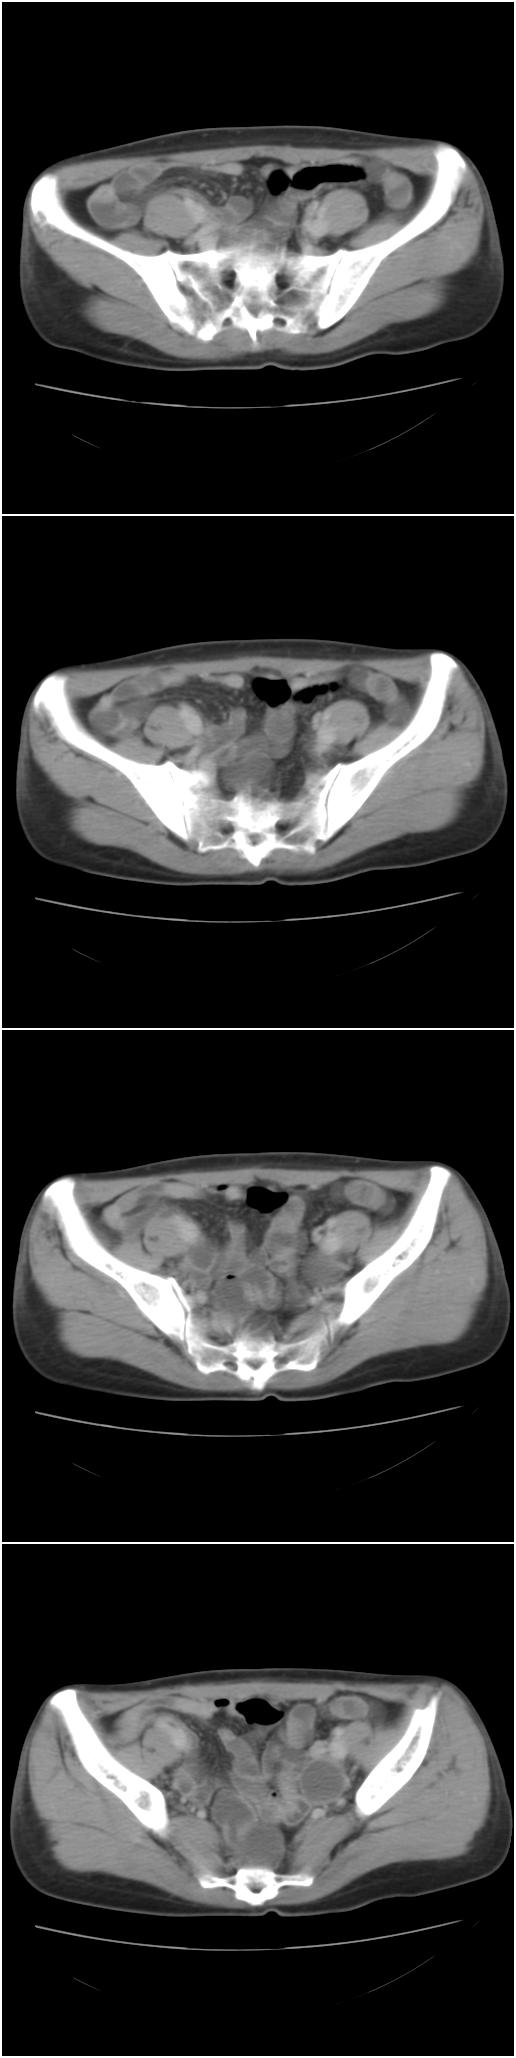

以下是今天的增强片,大家可以看看:

右髂骨见一类圆形略高密度区,似见分层,骨质破坏不明显

考虑良性病变,以动脉瘤样骨囊肿可能性大

右侧髂骨后缘囊状膨胀性骨质改变,无明显骨间隔,周围无明显硬化及骨膜反应,周围软组织无异常,相邻骨组织密度增高,考虑:动脉瘤样骨囊肿可能,要注意与骨巨细胞瘤及转移瘤鉴别。

囊性;密度均;未见分格;骨囊肿

右侧髂骨膨胀性骨质破坏区 囊内密度尚均匀 骨巨细胞瘤可能性大 动脉瘤样骨囊肿不除外 建议mr观察囊内成分明确诊断 左侧附件区包裹性积液

该病人今天做了增强,右侧髂骨病灶明显强化。

右侧髂后上棘局限性囊状骨质破坏,大部分界清,似见轻度硬化边,内无分格及钙化,病灶上部局部显示模糊。考虑;骨巨细胞瘤可能大,不除外abc。另可见子宫肌瘤术后子宫缺如。

临床和影像学表现:女性患者46岁,有子宫肌瘤手术病史。影像所见可见残余宫颈部分,左右附件未见新生物;右髂骨翼后端囊状膨胀性骨破坏,囊性部分感觉有强化(楼主标上增强前后的ct值就很好了),未见明确的液—液平面,周边硬化不明显或轻度硬化。

分析:患者年龄46岁,没有明确外伤病史,病变呈膨胀性骨破坏,囊性部分未见明确的液—液平面,周边硬化不明显。综合分析该病例比较符合骨巨细胞瘤,不太符合动脉瘤样骨囊肿。

诊断:1、首先考虑骨巨细胞瘤;2子宫肌瘤术后改变